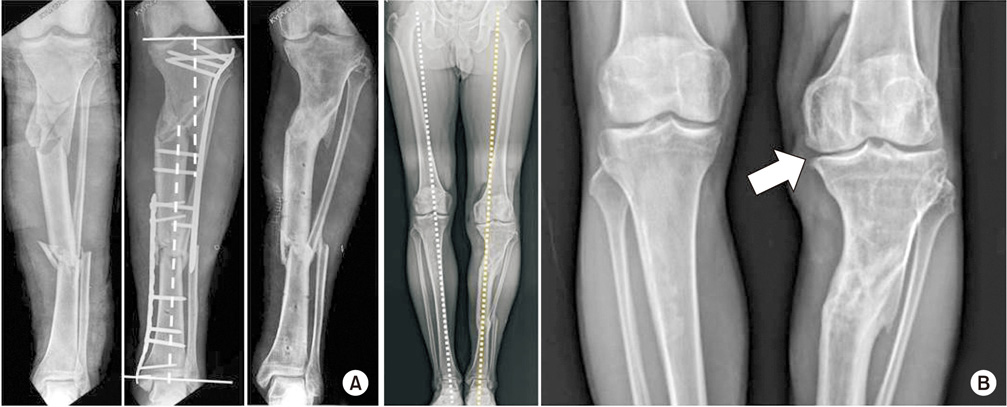

(A) A 24-year-old male underwent plate fixation due to fracture of the tibia, but angulation and displacement remained. After 12 years of injury, the bone was united. (B) A slight shortening of the lower limb and medial deviation of the mechanical axis were checked, and traumatic osteoarthritis was found in the medial compartment of the left knee compared to the right knee (arrow).

Fig. 1 (A) A 24-year-old male underwent plate fixation due to fracture of the tibia, but angulation and displacement remained. After 12 years of injury, the bone was united. (B) A slight shortening of the lower limb and medial deviation of the mechanical axis were checked, and traumatic osteoarthritis was found in the medial compartment of the left knee compared to the right knee (arrow).